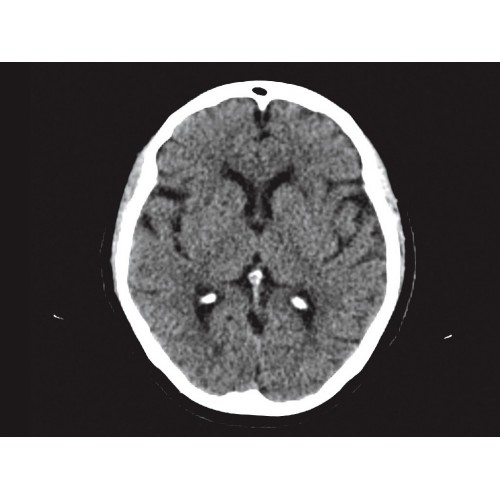

Компьютерный томограф GE Brivo CT385 представляет собой современное диагностическое оборудование, сочетающее высокую точность исследований с повышенным комфортом для пациентов. Этот аппарат открывает новые возможности для детальной визуализации анатомических структур.

Позволяет проводить комплексные исследования всех анатомических зон, включая нейровизуализацию, ангиографию, исследования органов грудной и брюшной полости. Особенно эффективен для раннего выявления онкологических заболеваний.

Специализированные исследования